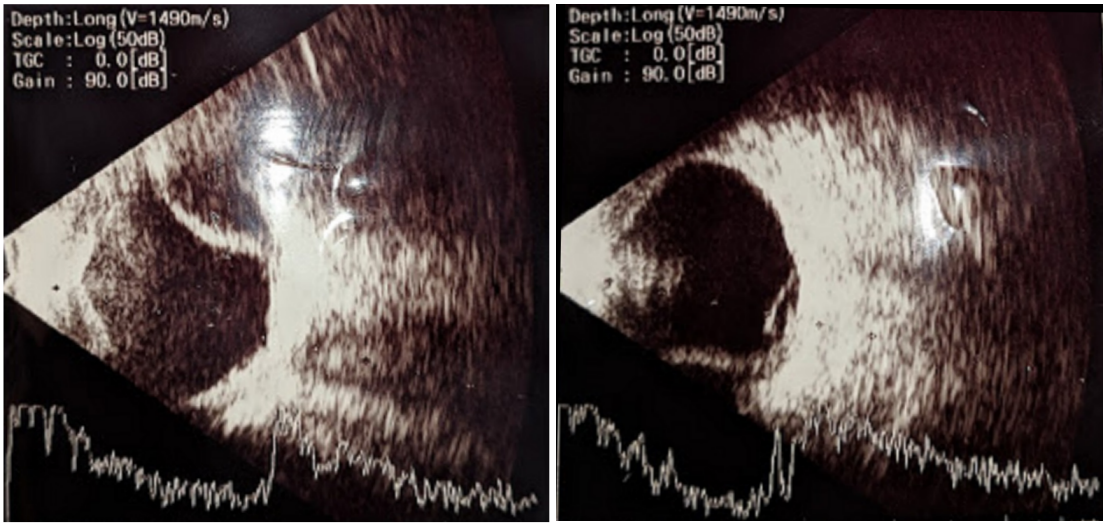

On the first postoperative day, the visual acuity was 3/60, the anterior chamber was shallow with choroidal detachment and exudative retinal detachment (Figure 2 [Fig. 2]). For this reason, oral prednisolone 1 mg per kg body weight as a single morning dose was added to the operative medications. The same was gradually tapered off over one month. On the fifth postoperative day, visual acuity improved to 6/60, slit-lamp examination showed a peripheral anterior chamber depth of ½ central corneal thickness. Intraocular pressure was 9 mmHg. Patient was continued on postoperative medications and follow-up visits. Subsequent visit one month postoperatively revealed a best corrected visual acuity of 6/9, a well-formed anterior chamber and normalization of intraocular pressure to 12 mmHg. Fundus examination showed resolution of choroidal and exudative retinal detachment (Figure 3 [Fig. 3]).

Figure 2: B-scan ultrasonography showing choroidal detachment and exudative retinal detachment on the 1st postoperative day

Figure 3: B-scan ultrasonography after 2 weeks in postoperative period showing resolution of choroidal and retinal detachments